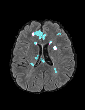

In recent years, data-driven machine learning (ML) methods have revolutionized the computer vision community by providing novel efficient solutions to many unsolved (medical) image analysis problems. However, due to the increasing privacy concerns and data fragmentation on many different sites, existing medical data are not fully utilized, thus limiting the potential of ML. Federated learning (FL) enables multiple parties to collaboratively train a ML model without exchanging local data. However, data heterogeneity (non-IID) among the distributed clients is yet a challenge. To this end, we propose a novel federated method, denoted Federated Disentanglement (FedDis), to disentangle the parameter space into shape and appearance, and only share the shape parameter with the clients. FedDis is based on the assumption that the anatomical structure in brain MRI images is similar across multiple institutions, and sharing the shape knowledge would be beneficial in anomaly detection. In this paper, we leverage healthy brain scans of 623 subjects from multiple sites with real data (OASIS, ADNI) in a privacy-preserving fashion to learn a model of normal anatomy, that allows to segment abnormal structures. We demonstrate a superior performance of FedDis on real pathological databases containing 109 subjects; two publicly available MS Lesions (MSLUB, MSISBI), and an in-house database with MS and Glioblastoma (MSI and GBI). FedDis achieved an average dice performance of 0.38, outperforming the state-of-the-art (SOTA) auto-encoder by 42% and the SOTA federated method by 11%. Further, we illustrate that FedDis learns a shape embedding that is orthogonal to the appearance and consistent under different intensity augmentations.